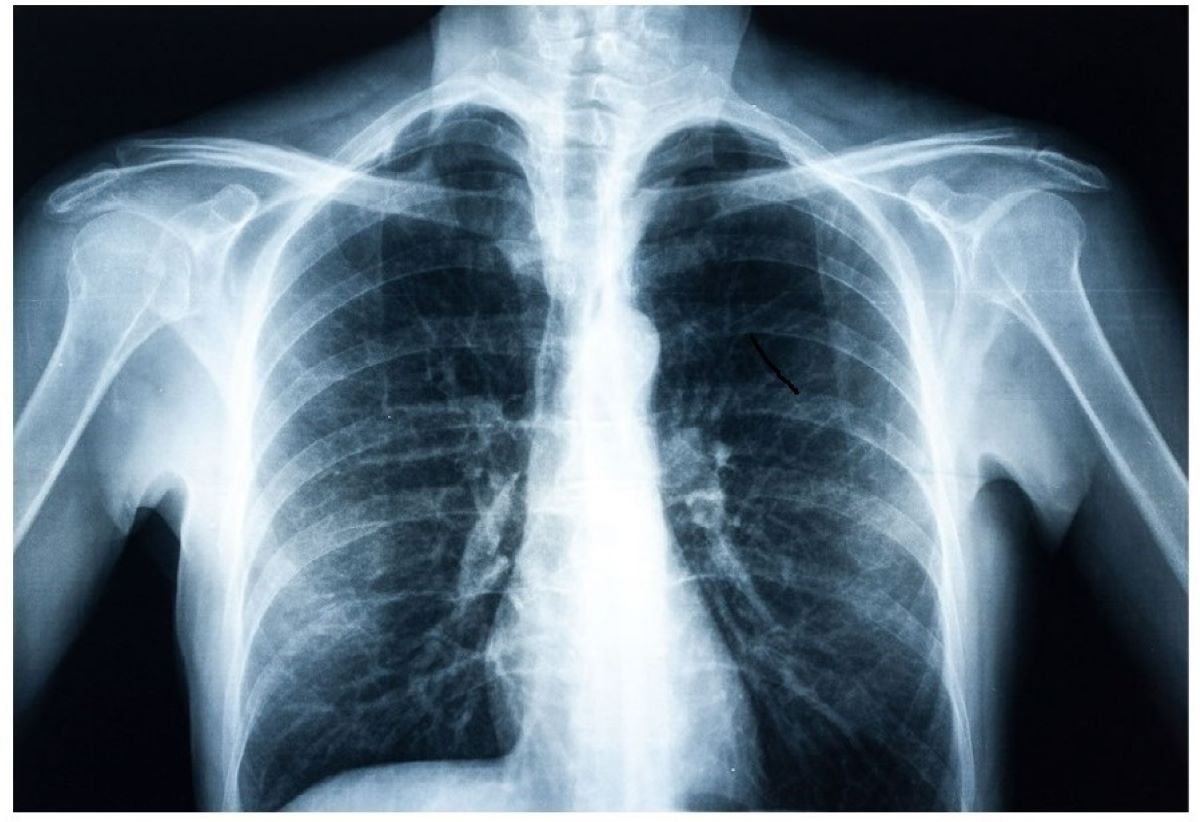

तर एउटा अनुसन्धानमा गल्ती गर्दा अरू नै कुरा आविष्कार भएका उदाहरणहरू समेत प्रशस्त छन् । जसमध्ये एक हो – एक्स रे । सन्की भौतिकशास्त्रीका रूपमा चिनिएका विलहेल्म रोन्टजेनले अर्कै काम गर्दागर्दै एक्स–रे आविष्कार गरेका हुन् ।

त्यसपछि उनले यसको प्रयोग श्रीमतिको हातमा गरे । सन् १८९५ नोभेम्बर ८ मा विलहेल्म रोन्टजेनले पहिलो पटक आफ्नी श्रीमतिको हातको एक्सरे फिल्म निकाल्न सफल पनि भए ।

उनको यो अविष्कारले रेडियोलोजिको शुरूवात गरेको हो। यही कारण अहिले नोभेम्बर ८ का दिन विश्व रेडियोलोजी दिवस मनाउन थालिएको छ । त्यहि आविष्कारका लागि सन् १९०१ मा नोबल पुरस्कार द्वारा उनलाइ सम्मानित गरिएको थियो।

यसरी एक्स–रेको आविष्कार भयो र शरीरभित्रका अंगको अध्ययनमा यसले ठूलो क्रान्ति ल्याइदियो ।